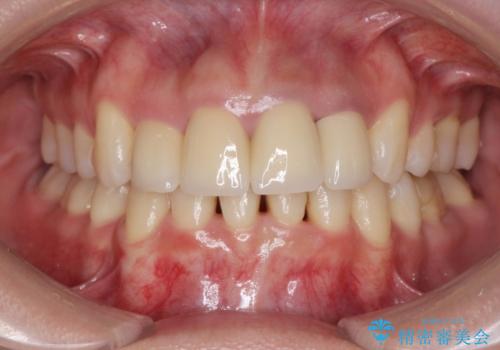

変色した歯を改善、セラミック治療

- 神経の死んでしまっている前歯の変色の改善を求めて来院されました。

根管治療をしたのち時間が経過して変色が目立つ歯と、レジン充填が複数箇所に及んでいる歯も同時にオールセラミック治療を行っていくこととなりました。

自然な歯の色に仕上げることができ、大変喜んでいただくことができました。